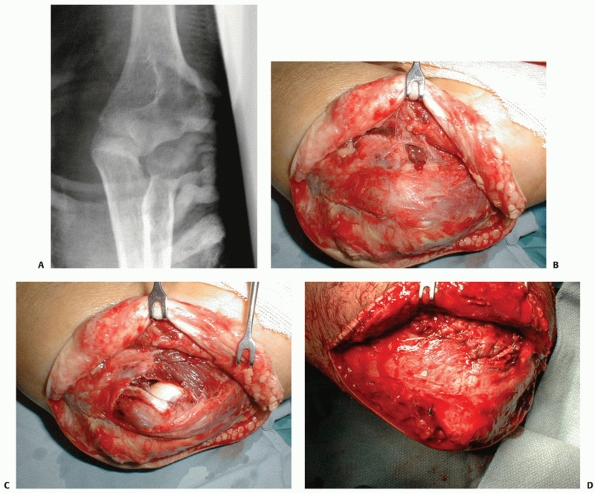

|

FIGURE 32-20 Posterior olecranon fracture-dislocations can be very complex injuries. A. In this patient, the coronoid and radial head are fractured. B. The coronoid is split into three fragments. (continues)

![]() |

FIGURE 32-20 (Continued) C. A posterior skin incision discloses muscle injury. D.

If the muscle injury is opened up and extended somewhat, the olecranon fragment can be translated proximally like an olecranon osteotomy, exposing the elbow articulation. E. An additional medial exposure with transposition of the ulnar nerve helps with manipulation of the anteromedial fracture fragment. F. The coronoid is split into three large fragments: anteromedial, central, and lesser sigmoid notch. G. A long dorsal plate is applied, bridging the comminution and securing the coronoid. H. The radial head is replaced. I. The anteromedial portion of the coronoid is secured with screws. Healing occured and good elbow function was restored. |